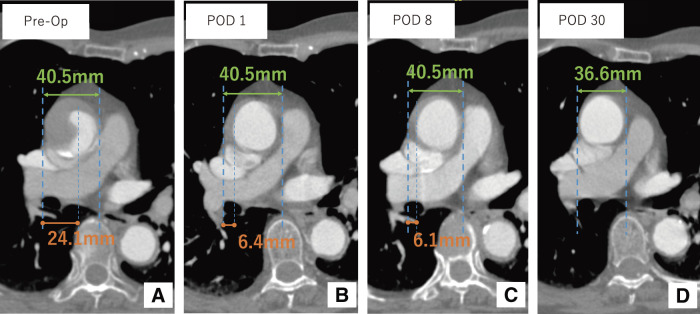

Iatrogenic type A aortic dissection (TAAD) is a rare but potentially fatal complication of coronary angiography. We report a case of iatrogenic retrograde TAAD originating from the right subclavian artery. Endovascular entry closure using a stent graft led to resolution of the false lumen and favorable aortic remodeling. The patient remained free from cardiovascular events over a 4-year follow-up. This case highlights the potential efficacy of endovascular treatment, even in retrograde TAAD with its entry located in the subclavian artery.